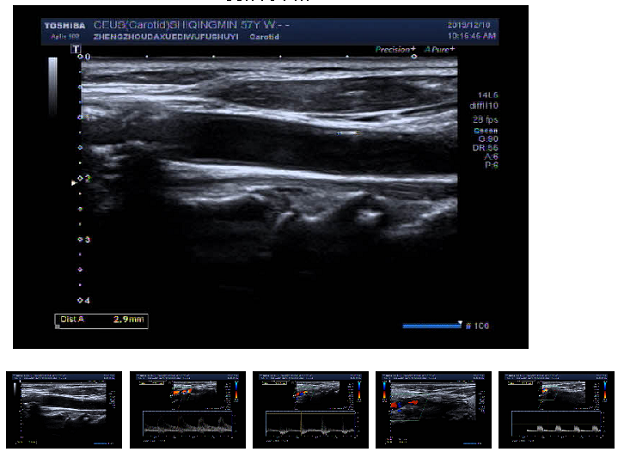

近些年,随着我国国民健康意识的提高,许多中老年人都愿意在定期体检中把颈动脉彩超列为必选项。检查结果有时会提示颈动脉斑块形成(图一、图二),这让一些中老年朋友非常紧张,因为他们知道斑块是导致中风(脑卒中)的原因。那么,这种担心是否必要呢?今天,小编就带领大家一起来认识一下颈动脉斑块这一病变。

▲ 图一

动脉是血液流通的管道,心脏的血液就是随着动脉流向各个脏器提供能量和氧分,这个管道的好坏影响着血液是否能够正常流通、脏器是否能得到充足的血液(图三)。而动脉这个管道并不是永远会保持畅通的,随着人年龄的增长和各种危险因素的影响,管道会逐渐老化,主要表现为动脉内膜增厚和斑块的形成,而颈动脉又是最容易形成斑块的区域,所以该处的斑块形成能够反映人动脉粥样硬化的程度。(图四)